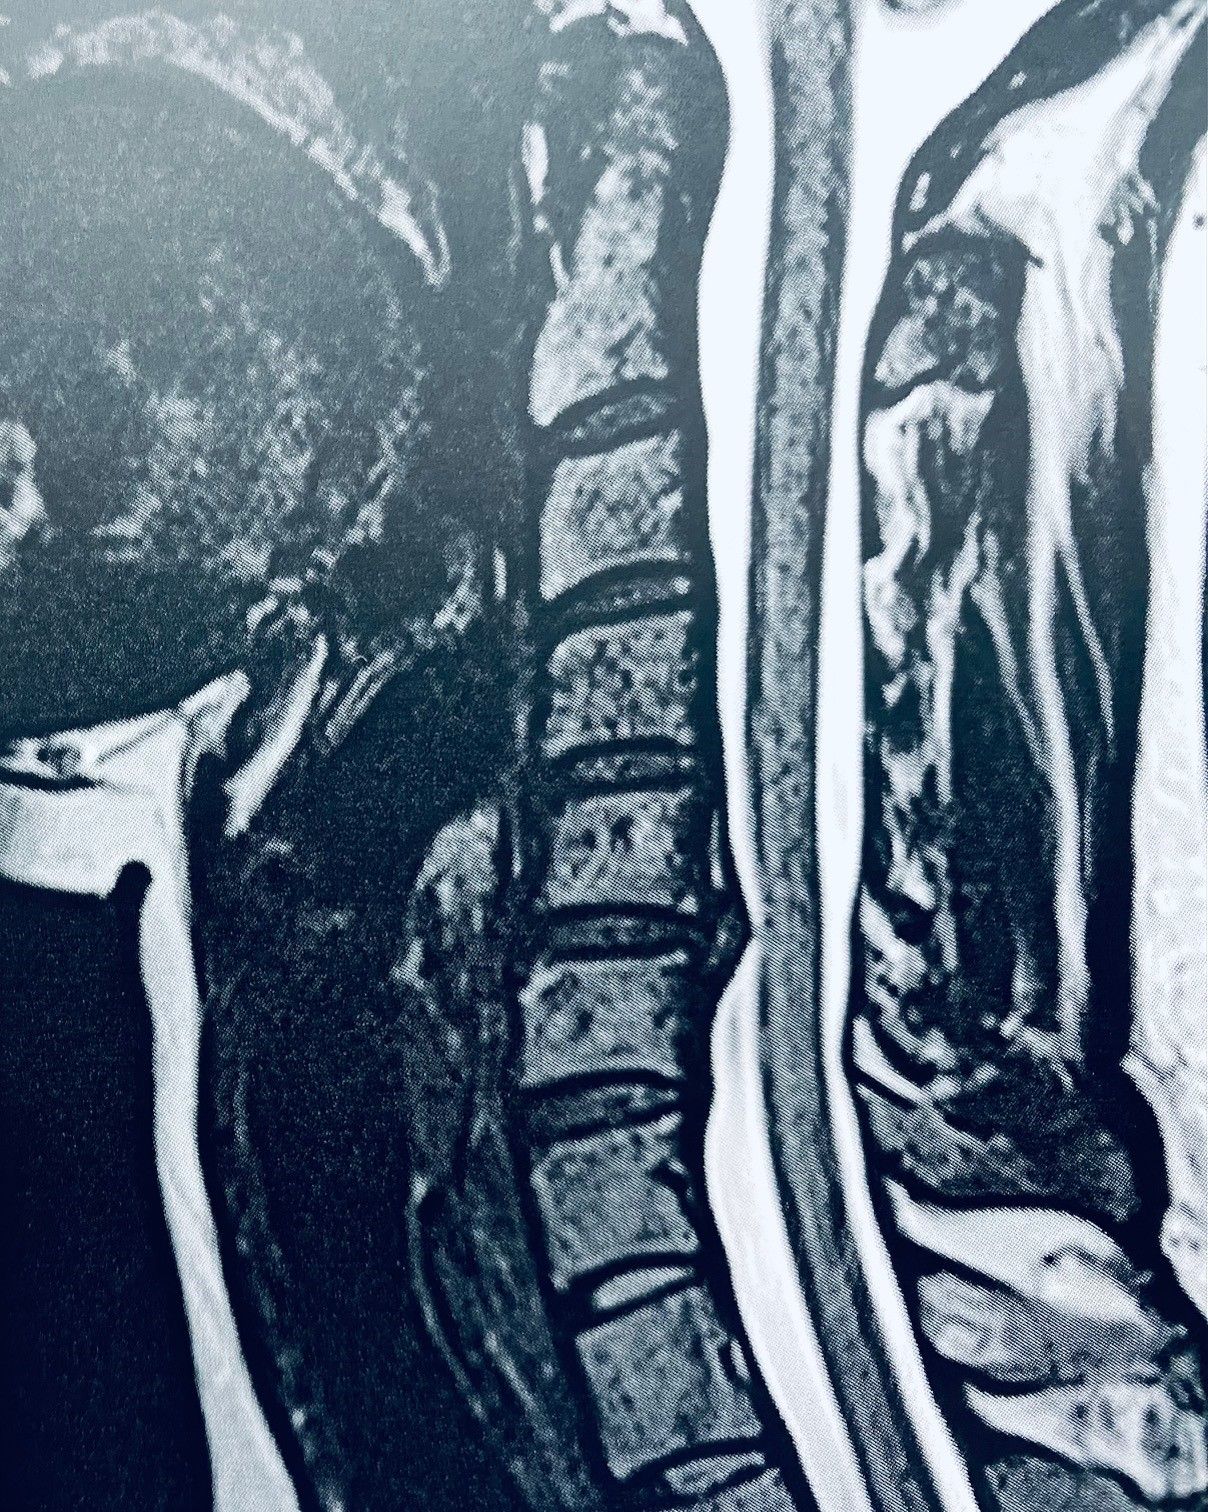

Como especialista em Neurocirurgia faço tratamentos de doenças relacionadas ao Sistema Nervoso Central como tumores, patologias vasculares, traumatismo e Infecções que necessitem de uma abordagem cirúrgica ou acompanhamento Clínico.

Sou especialista em Cirurgia da Coluna Vertebral e Medicina da Dor em que faço tanto tratamentos clínicos quanto cirúrgico.

• Cirurgia da Coluna Cervical

• Doenças Da Coluna Vertebral

• Compressão Da Medula Espinal

• Cervicalgia

• Estenose Espinal

• Doenças Da Medula Espinal